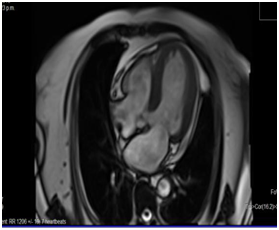

Magnetic resonance imaging

Four chamber apical cut at T2 phase where we observe an absence of a late highlight of the left ventricle (Figure 5). Short axis apical cut at black sequence phase where we observe a hyperintense highlight at the apical endocardium (Figure 6).

Figure 5